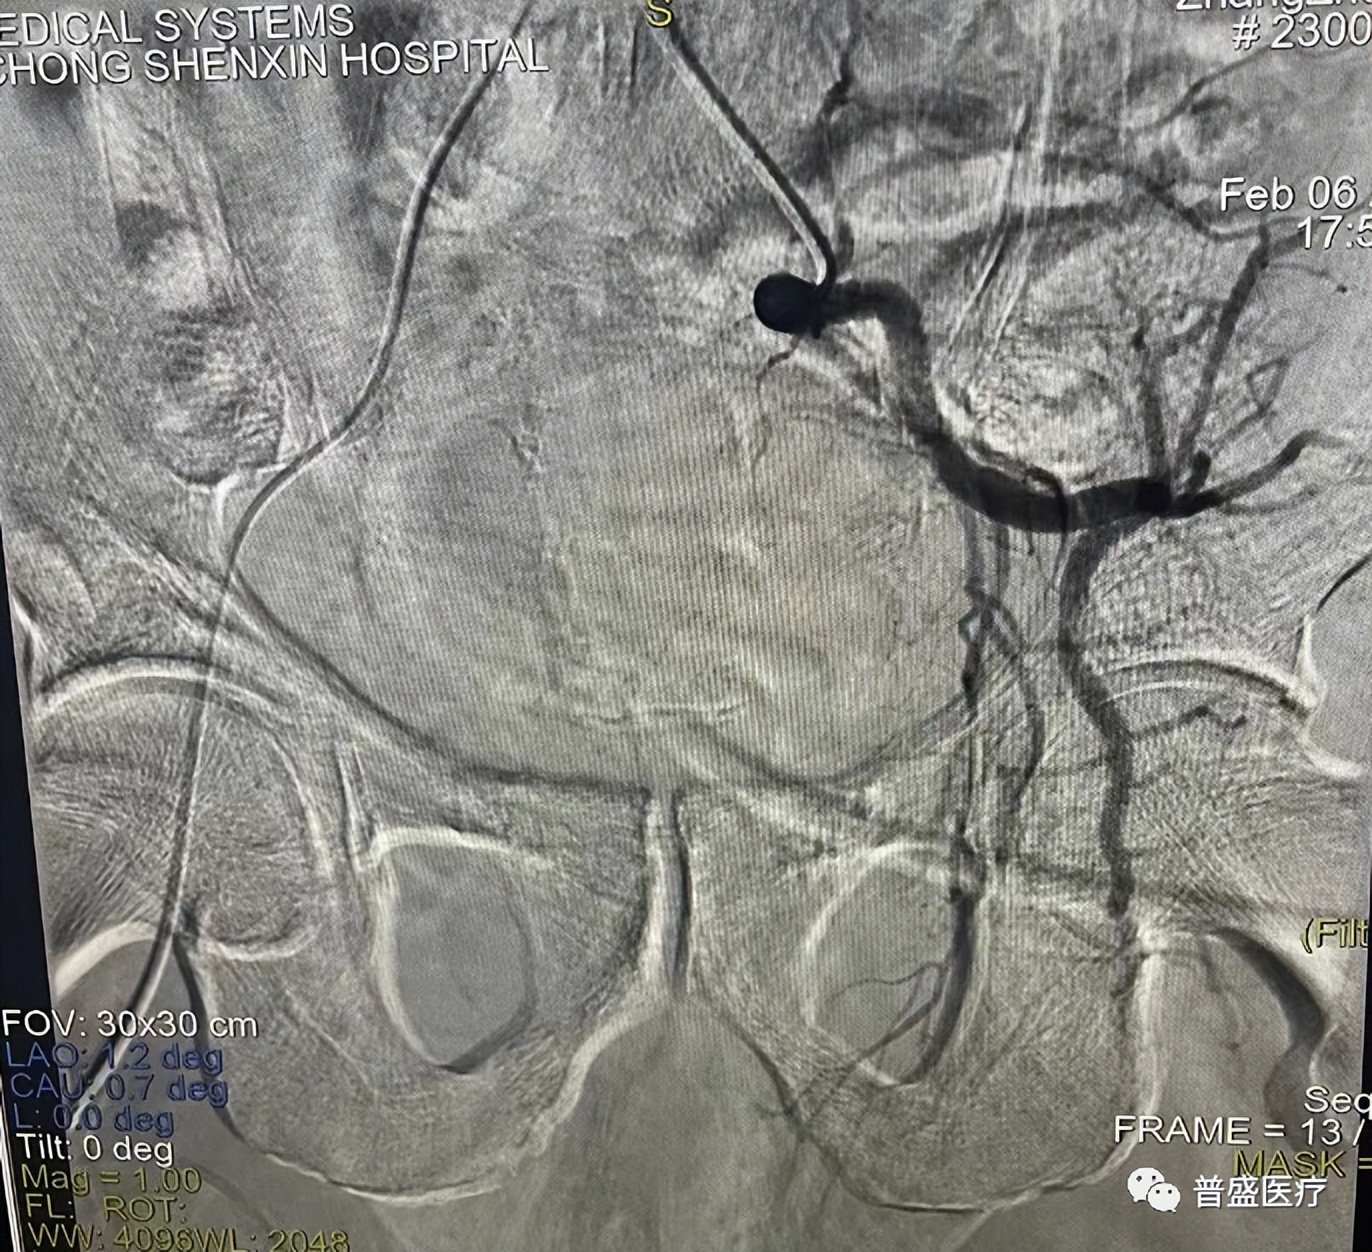

左侧子宫动脉栓塞前↑

左侧子宫动脉栓塞后↑

宫颈癌的介入治疗在临床上多将灌注化疗与栓塞相结合形成动脉灌注化疗栓塞术,栓塞的目的是使对血供敏感的肿瘤细胞缺血缺氧,从而致使肿瘤坏死,因此动脉栓塞术在宫颈癌的介入治疗中扮演着重要角色。

进行细致检查并详细研究病情后,确定可以通过宫颈癌化疗栓塞术进行治疗。通过经股动脉引入一根导管,将导管分别置入双侧子宫动脉,在DSA(血管造影系统)下对瘤体的供养血管进行栓塞,中断恶性肿瘤的供血后注射化疗药物直达病灶。该手术时间不到半个小时,患者生命体征平稳,安返病房。临床效果十分理想。